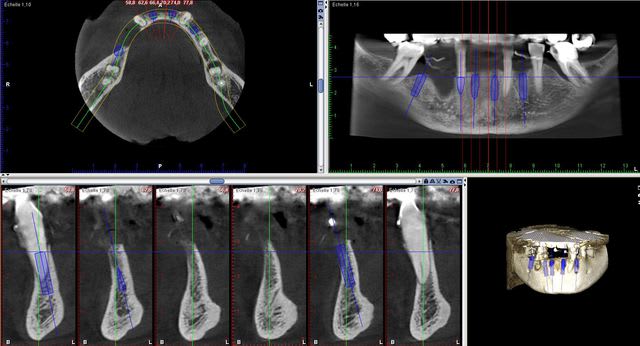

Chez ce patient des implants sont prévus à la mandibule.

La 3D de controle avec des implants 3.3*12

Ma question ne porte pas tellement sur le plan de traitement mais plutot sur l'approche du secteur anterieur 43 à 32